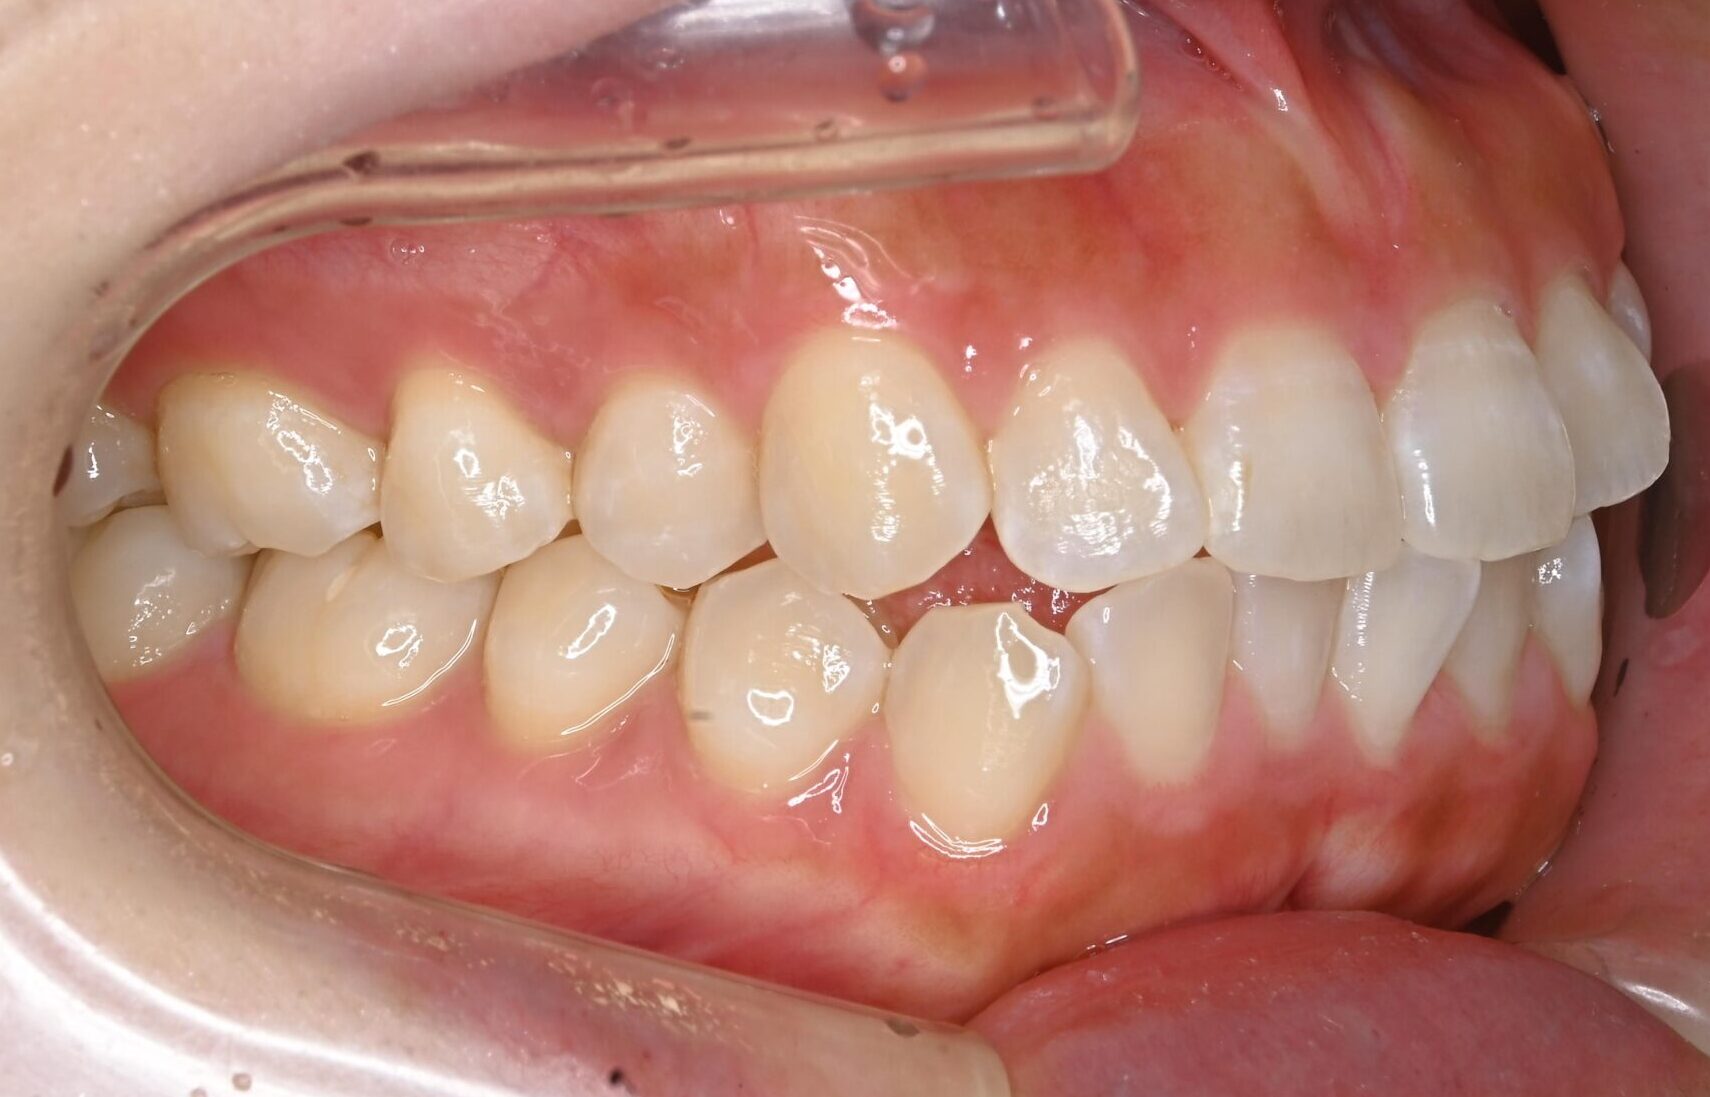

症例写真 before